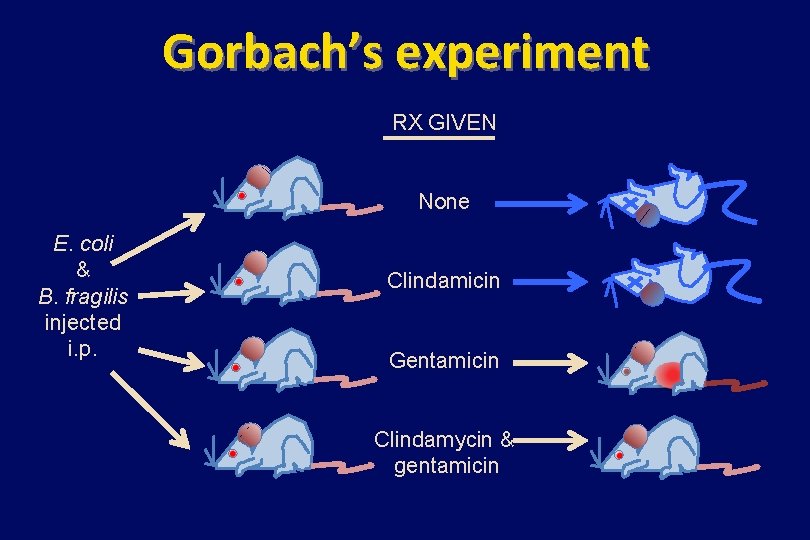

Gorbach’s experiment RX GIVEN None E. coli & B. fragilis injected i. p. Clindamicin Gentamicin Clindamycin & gentamicin